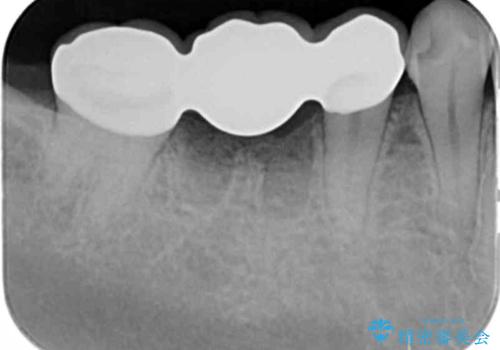

インプラント治療ではなく手術の必要のないブリッジ治療を希望・選択されたので治療を進めます。

- 36.3万円(仮歯・ジルコニアクラウン×3)費用は治療当時の料金となります

最終的なクラウンを入れずコアのまま、仮歯のまま長期間過ごすと虫歯が再発し残すことが難しくなってしまうことがあります。